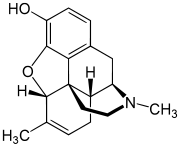

Opium alkaloids and derivatives

Phenanthrenes naturally occurring in (opium):